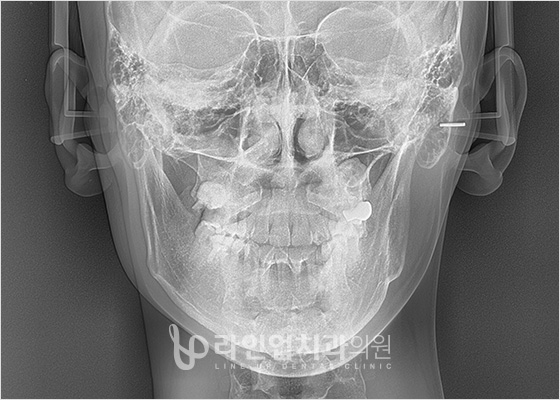

Before and After

Before

After